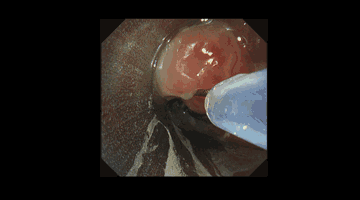

入院后,王洪武主任结合患者身体情况,制定周密的手术方案,在气管镜室内,行支气管镜治疗。全麻下经口进硬镜,气管切开口上端可见一肉芽肿,“横”在气道中间,使管腔狭窄约80%。王洪武主任遂即给予圈套器套取、并采用低温等离子将肉芽大部分清除,管腔较前明显增宽,狭窄约10%。一个小时后,杨阿姨狭窄处气道明显扩大,通气得到显著改善,手术顺利完成。

圈套器套取肿物